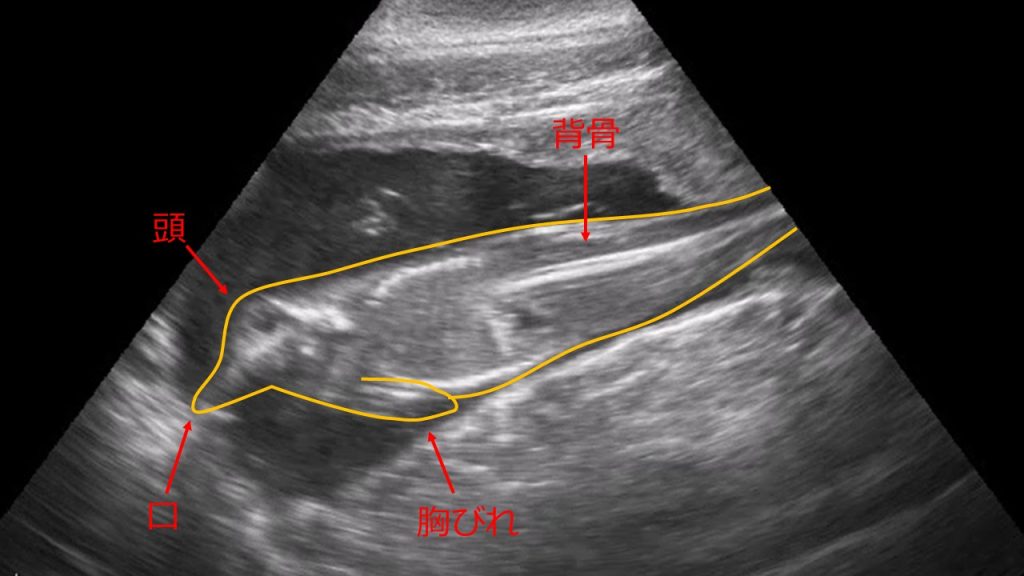

5 超音波(エコー)画像 (撮影日:令和7年10月1日)

胎仔が動く様子も確認しています